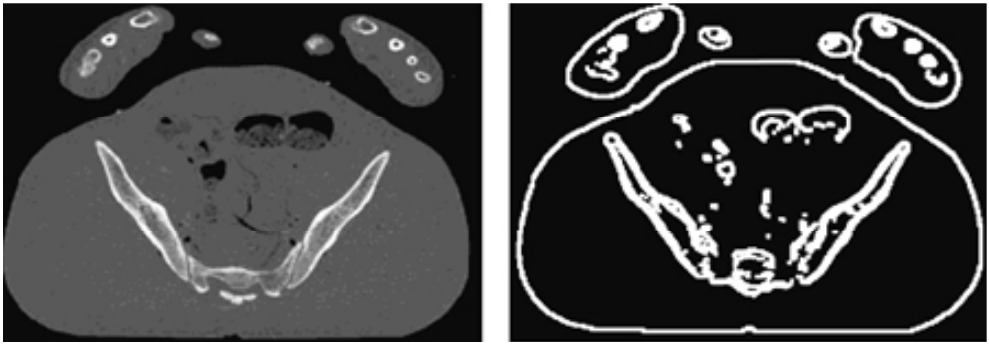

- 필터링이 된 이미지는 Mean-Shift Segmentation 알고리즘을 사용하여 Segment로 분할된다. 작은 Segment는 가장 유사한 인접 Segment로 병합된다. Image Segmentation을 통해 뼈를 쉽고 빠르게 식별하고 표시할 수 있다.

- 그 후 Canny edge detector를 사용하여 edge를 추출한다. (아래 그림 참고) Canny edge detector는 스케일 위치를 계산할 때 적합한 시작점이다.